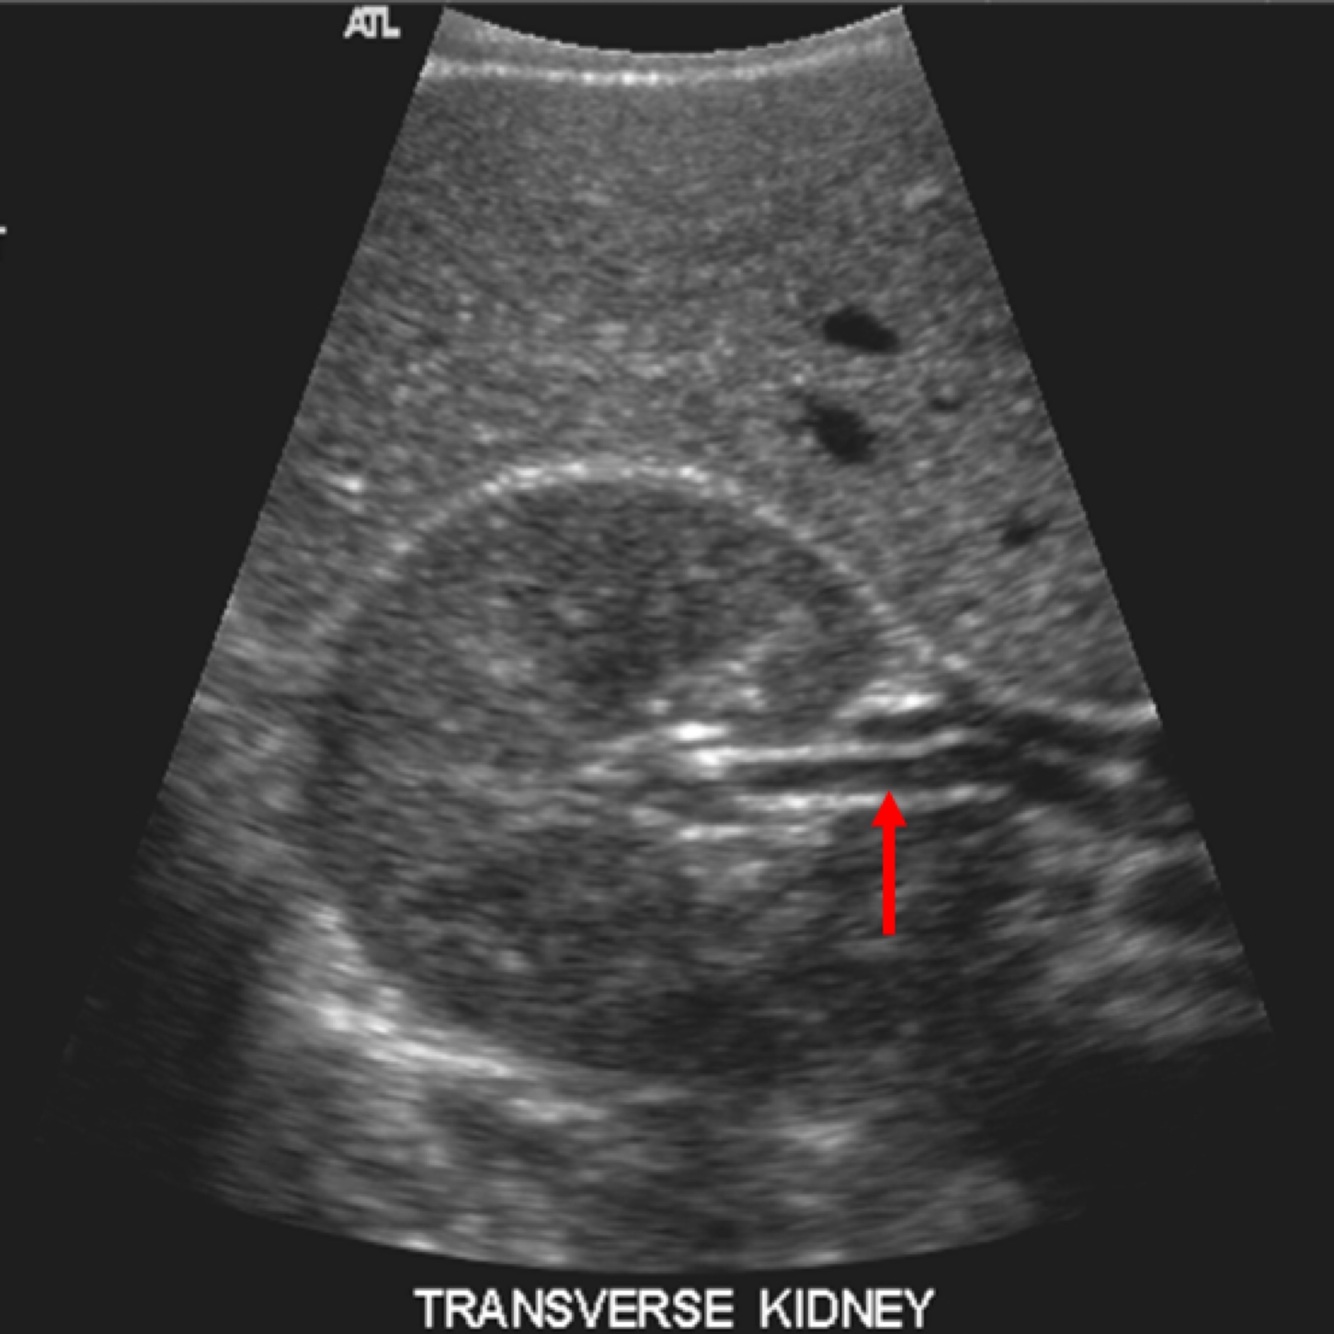

The area indicated by the arrow is what?

A

1. The CM junction

2. The arcuate junction

3. A landmark for cortical thickness